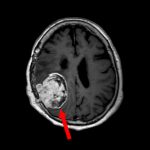

下垂体腺腫

No.’25_102 摘出 前